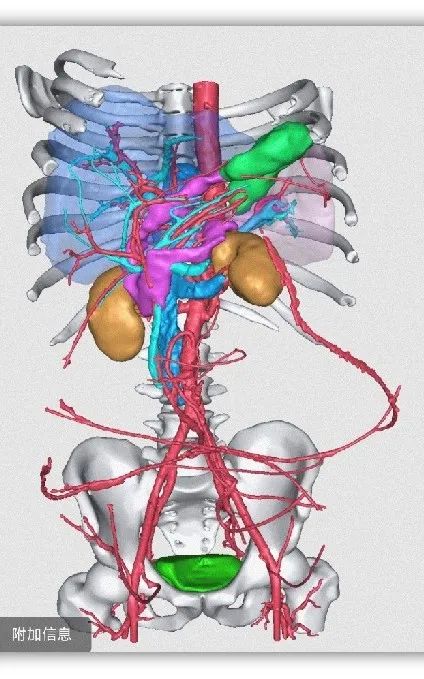

三维重建

考虑到患者肿瘤巨大,其腹围达到119cm,占据全腹腔和盆腔,暴露十分困难;重要脏器和血管均有明显推挤移位,没有正常解剖结构,手术风险极大,易造成副损伤;肿瘤生长时间长,侵及腹腔多脏器,与腹部大血管、神经、输尿管、胃肠道关系紧密,需要行多脏器联合切除,手术难度极大。经与家属充分沟通后,团队最终决定“以血管为导向”,行根治性“腹膜后巨大肿瘤切除+左肾切除+降结肠切除+肠肠吻合术”。

3月11日,老李被推进手术室。岳树强教授、刘正才副教授、李霄副主任医师等精准施术。术中探查结果和术前腹部影像、三维重建影像资料,均证实患者腹部脂肪肉瘤同样起源于左肾脂肪囊。

时间一分一秒流逝,在团队默契协作下,难题逐个攻破。患者左侧腹膜与肿瘤黏连,团队小心游离,采用线手套将肿瘤整体推向左侧,显露右侧根部并寻找血管边界,继而以重要大血管为指引,显露、解剖、裸化“下腔静脉、腹主动脉、左肾动静脉”至左右侧髂血管,最终完整切除肿瘤,手术历时4小时45分钟顺利结束。术中出血仅1700ml,输注RH+B型去白细胞悬浮红细胞10U、病毒灭活冰冻血浆1350ml。